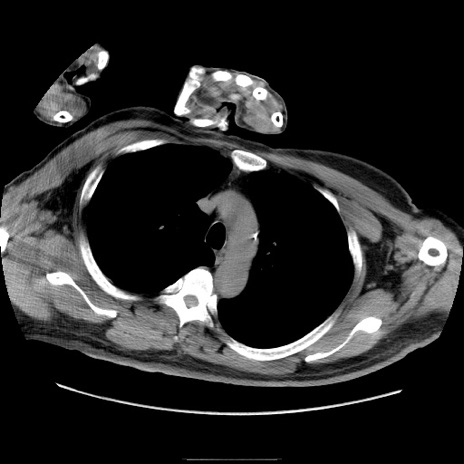

症例22(横断像)

【症例】50歳代男性

【主訴】腹痛

【現病歴】AVMからの被殻出血のため回復期リハ病棟入院中。 本日午後3時頃急に下腹部痛が出現した。

【既往歴】AVM、被殻出血、虫垂炎、高血圧

【身体所見】意識晴明、左半身不全麻痺、会話の理解は良好、36.5°C、腹部:膨隆、全体に板状硬、下腹部正中に圧痛点あり、反跳痛-、筋性防御不明、右下腹部にope scar

【データ】WBC 9400、CRP 0.06